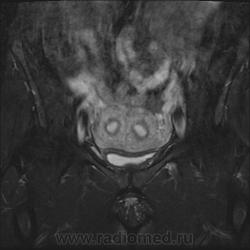

Удвоение матки.

Полное удвоение матки. Случайная находка. Женщина рожавшая, была весьма удивлена.